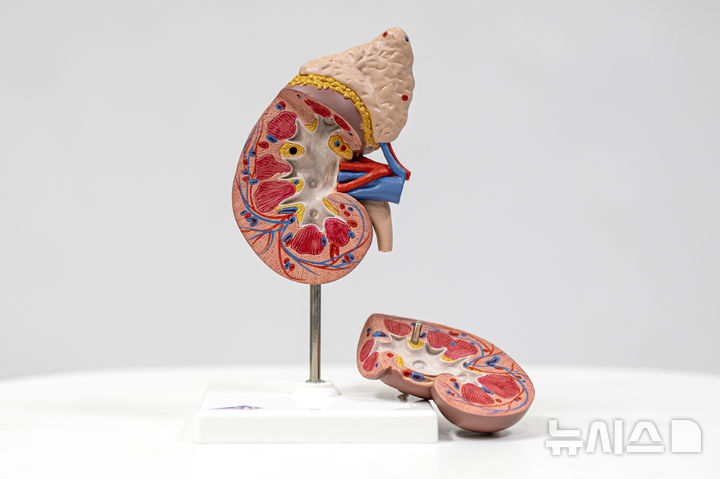

[서울=뉴시스] 지난 19일(현지시각) 미국 뉴욕포스트는 학술지 '사이언티픽 리포트'에 게재된 연구를 인용해서 생리혈이 골관절염 치료에 도움을 줄 수 있다고 보도했다. (사진=유토이미지)

지난 19일(현지시각) 미국 뉴욕포스트는 학술지 '사이언티픽 리포트'에 게재된 연구를 인용해서 생리혈이 골관절염 치료에 도움을 줄 수 있다고 보도했다.